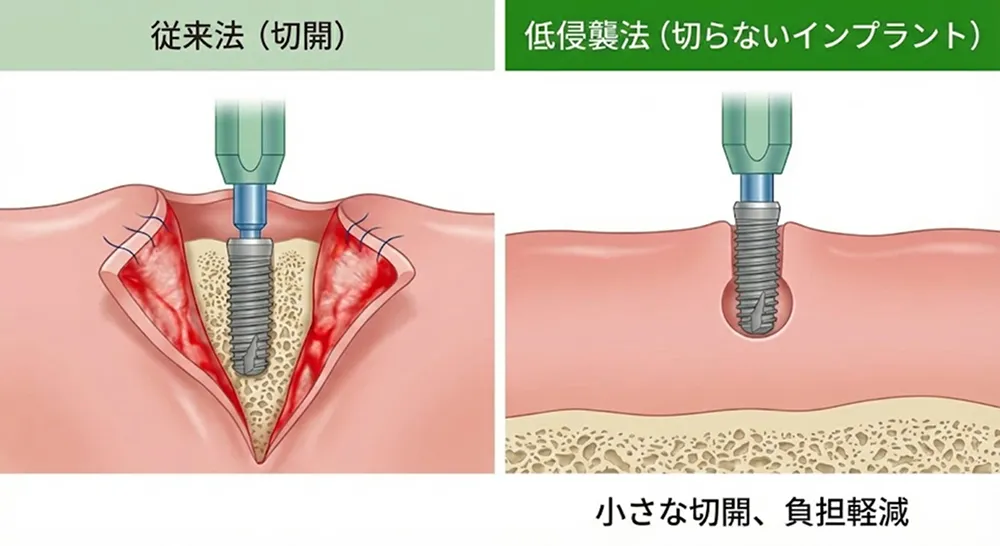

特徴② 切開を抑えることを目指したインプラント治療

従来のインプラント手術では、歯茎を大きく切開して骨を露出させる方法が一般的でした。しかし当院では、精密検査とシミュレーションによって歯茎の中の状態を十分に把握することで、症例によっては歯茎の切開を最小限に抑えることが可能です。

切開を小さくすることで、術後の痛みや腫れが軽減され、患者さんの精神的・肉体的な負担を大幅に軽くすることができます。

※すべてのケースで適用できるわけではありません。精密検査の結果、従来の方法が適切と判断される場合もあります。